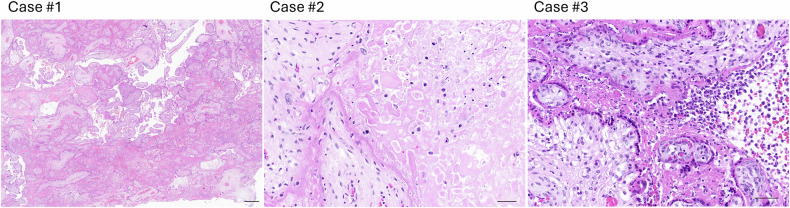

妊娠与严重COVID-19风险增加有关。此外,妊娠期感染SARS-CoV-2与不良的产科结局和胎盘异常有关。然而,早期滋养层细胞对SARS-CoV-2的易感性以及感染对滋养层细胞功能的潜在影响尚不清楚。在这项研究中,我们评估了妊娠早期滋养细胞对SARS-CoV-2感染的容性及其对滋养细胞融合的影响。为了解决这个问题,我们从妊娠早期的人胎盘中分离出原代细胞滋养细胞(CTB)细胞,并使其在体外分化为STB。这些细胞感染了相关的SARS-CoV-2变体,包括Delta和Omicron (BA.1, BA.2, BA.5)。采用RT-qPCR和免疫荧光技术评估病毒复制,同时采用RT-qPCR检测宿主细胞反应,包括病毒进入受体和先天免疫基因的表达。通过染色和计算融合指数来评估滋养细胞的融合。同时,通过免疫组织化学分析了感染sars - cov -2的孕妇的胎盘组织,以量化体内合胞结(SK)的形成。我们的研究结果表明,妊娠早期的CTB和STB都以变体和供体依赖的方式允许SARS-CoV-2感染,与Omicron变体相比,Delta表现出更高的复制效率。在STB中,病毒复制与诱导进入受体或III型干扰素反应无关。然而,在CTB中,病毒复制与增强的细胞融合显著相关。同时,与来自同一胎盘的未感染区域和胎龄匹配的对照组相比,在体内感染的胎盘区域中观察到SK的数量增加。总之,这些体外和体内结果表明,妊娠早期感染SARS-CoV-2可能会改变STB的转化,可能导致胎盘功能障碍和不良妊娠结局。

Pregnancy is associated with an increased risk of severe COVID-19. In addition, SARS-CoV-2 infection during gestation has been linked to adverse obstetrical outcomes and placental abnormalities. Nevertheless, the susceptibility of early trophoblast cells to SARS-CoV-2 and the potential consequences of infection on trophoblast function remain unclear. In this study, we assessed the permissiveness of first trimester trophoblast cells to SARS-CoV-2 infection and its impact on trophoblast cells fusion. To address this, we isolated primary cytotrophoblast (CTB) cells from first trimester human placentas and allow their differentiation into STB in vitro. These cells were infected with SARS-CoV-2 variants of concern, including Delta and Omicron (BA.1, BA.2, BA.5). Viral replication was assessed by RT-qPCR and immunofluorescence, while host cell responses, including expression of viral entry receptors and innate immunity genes, were measured by RT-qPCR. Trophoblast fusion was evaluated by staining and calculating the fusion index. In parallel, placental tissues from SARS-CoV-2-infected pregnancies were analyzed by immunohistochemistry to quantify syncytial knots (SK) formation in vivo. Our results demonstrate that both first trimester CTB and STB are permissive to SARS-CoV-2 infection in a variant- and donor-dependent manners, with Delta exhibiting higher replication efficiency compared to Omicron variants. In STB, viral replication did not correlate with the induction of entry receptors or type III interferon responses. However, in CTB, viral replication was significantly associated with enhanced cell fusion. In parallel, an increased number of SK was observed in infected placental areas in vivo compared to non-infected regions from the same placenta and to gestational age-matched controls. Altogether, these in vitro and in vivo results suggest that SARS-CoV-2 infection in early pregnancy may alter STB turnover, potentially contributing to placental dysfunction and adverse pregnancy outcomes.